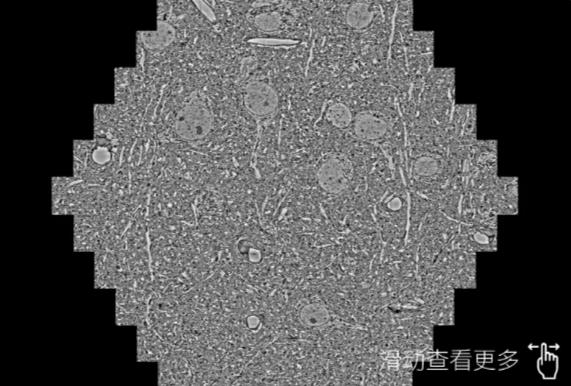

鼠脑切片。左图使用丰都蔡司丰都扫描电镜MultiSEM706对165μmx143pm面积区域成像,耗时仅需1.5秒。右图为鼠脑切片中30μm区域放大效果。样品由芝加哥大学B.Kasthuri提供。